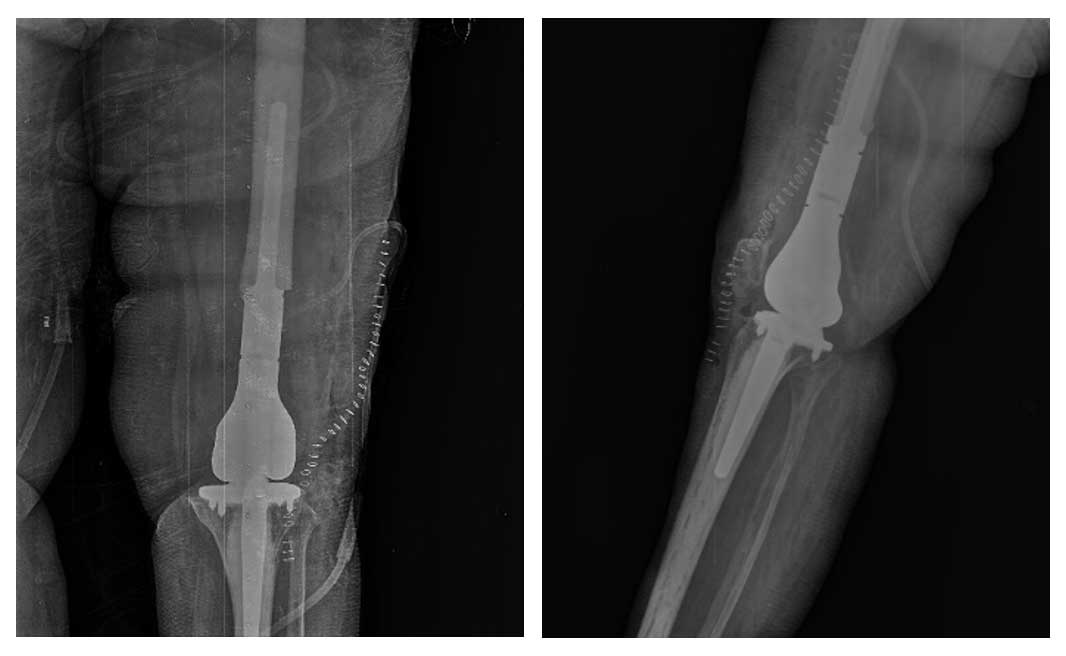

Vaka 44: Akciğer Kanseri Sol Uyluk (Femur) Alt Uç Metastazı

Ameliyat Sonrası: Röntgende çimentolu distal femur tümör protezi uygulanımı görülmekte.